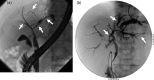

IgG4-related sclerosing cholangitis (IgG4-SC) is a distinct type of cholangitis frequently associated with autoimmune pancreatitis and currently recognized as a biliary manifestation of IgG4-related disease. Although clinical diagnostic criteria of IgG4-SC were established in 2012, differential diagnosis from primary sclerosing cholangitis and cholangiocarcinoma is sometimes difficult. Furthermore, no practical guidelines for IgG4-SC are available. Because the evidence level of most articles retrieved through searching the PubMed, Cochrane Library, and Igaku Chuo Zasshi databases was below C based on the systematic review evaluation system of clinical practice guidelines MINDS 2014, we developed consensus guidelines using the modified Delphi approach. Three committees (a guideline creating committee, an expert panelist committee for rating statements according to the modified Delphi method, and an evaluating committee) were organized. Eighteen clinical questions (CQs) with clinical statements were developed regarding diagnosis (14 CQs) and treatment (4 CQs). Recommendation levels for clinical statements were set using the modified Delphi approach. The guidelines explain methods for accurate diagnosis, and safe and appropriate treatment of IgG4-SC.